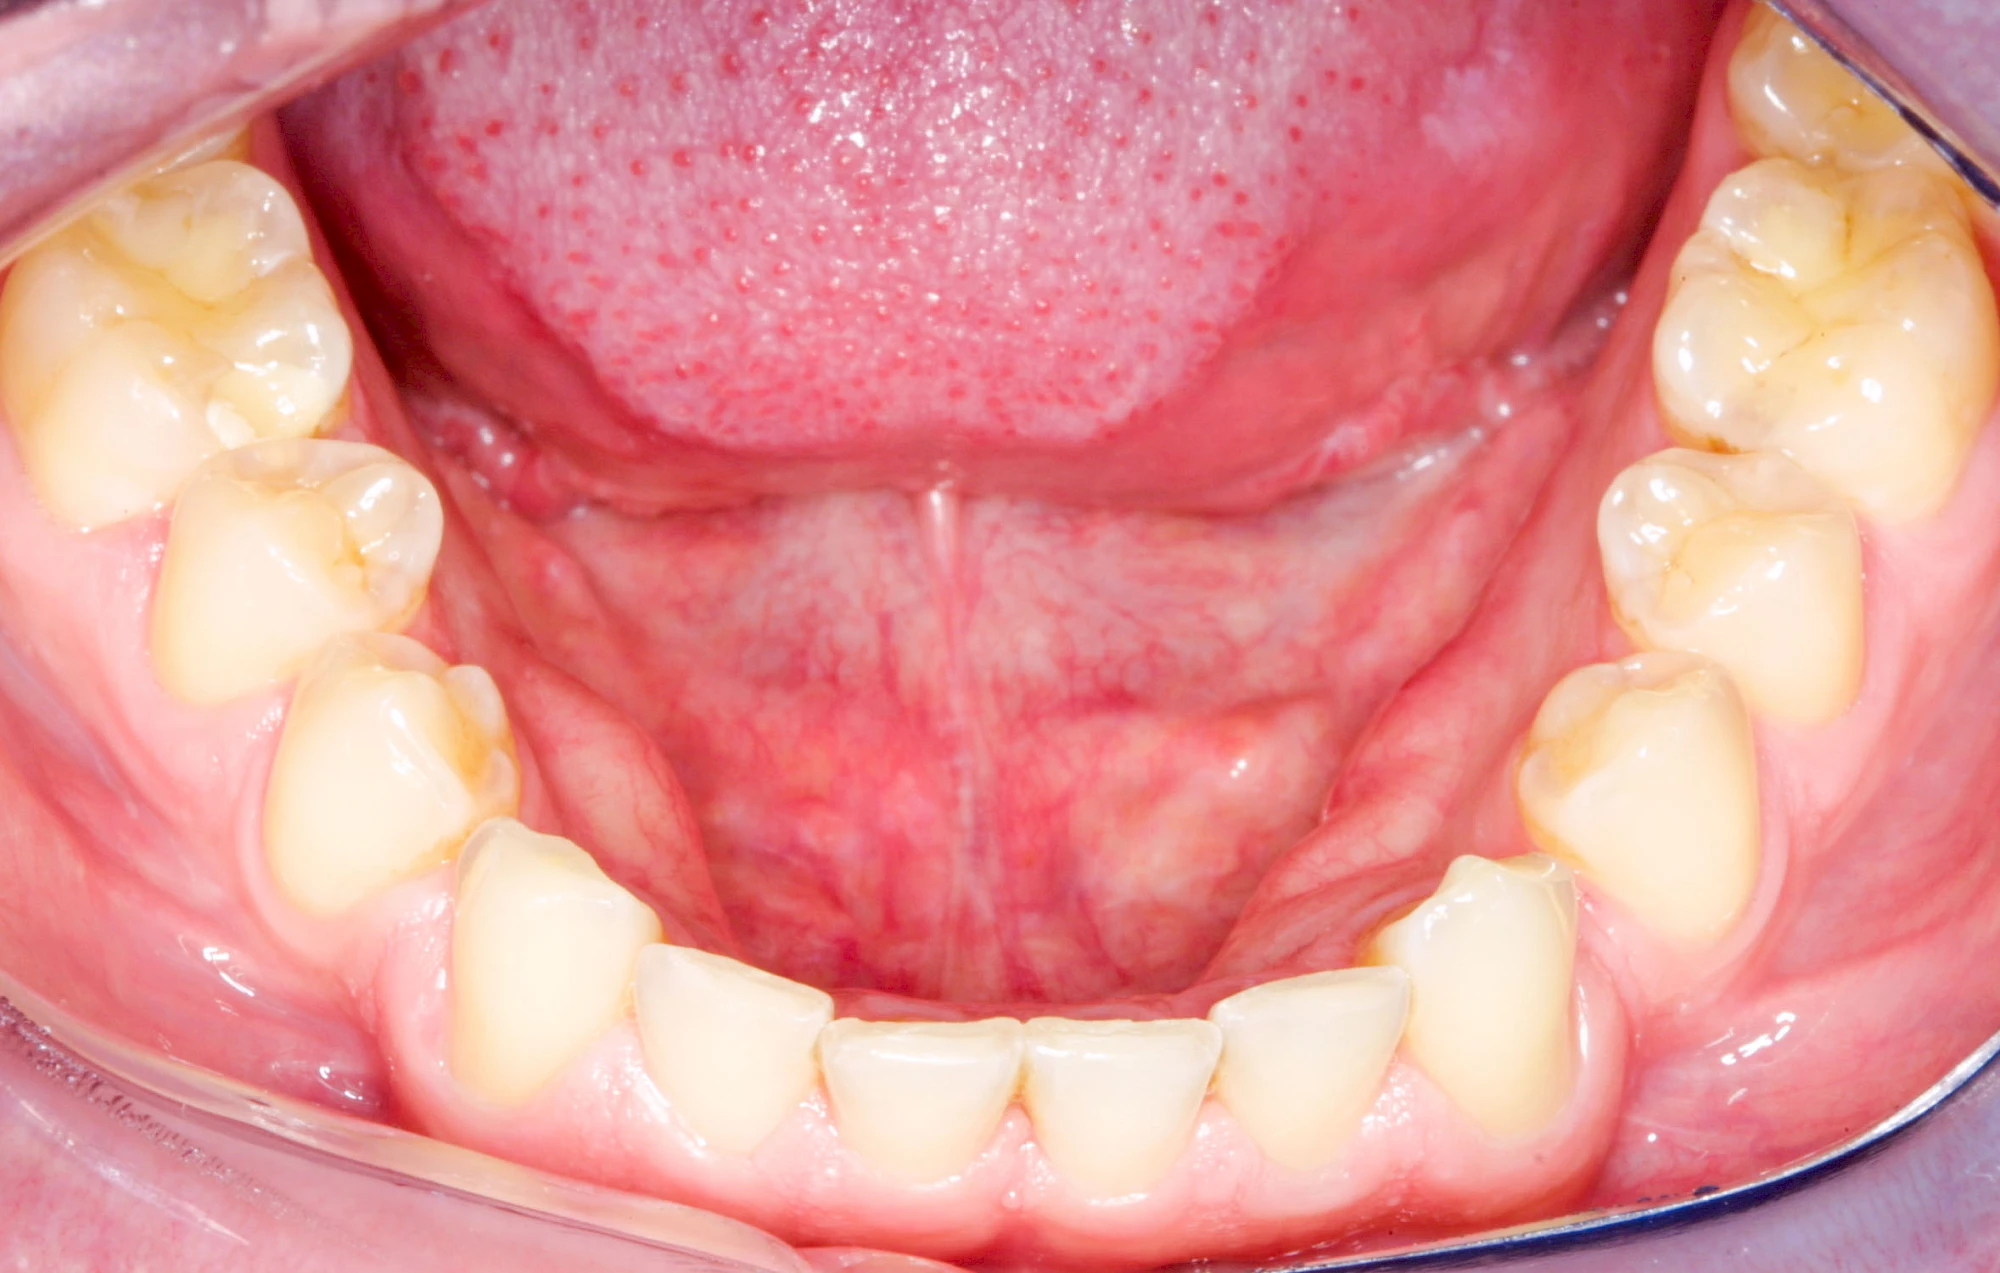

Überbein (Exostose)

Überbeine im Bereich der Kiefer sind gar nicht so selten. Häufiger im Bereich der Seitenzähne unterhalb des Zahnfleisches, aber auch in der Mitte vom Gaumen. Überbeine haben in dem Sinne keinen Krankheitswert, müssen also nicht operativ entfernt werden, wenn diese nicht stören. Überbeine können ein Anzeichen für Knirschen und Pressen sein.